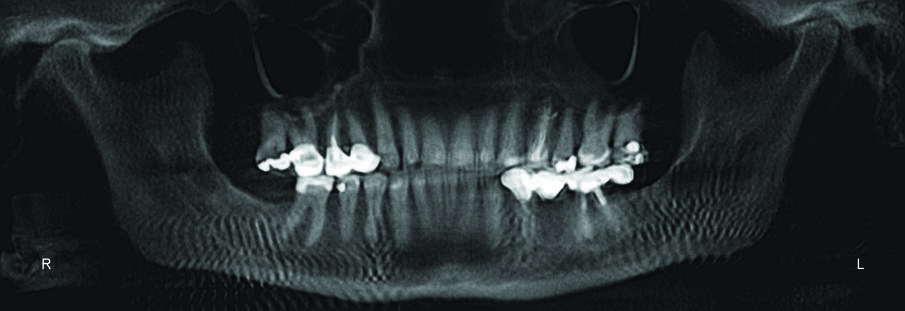

Her dental spacing was worse than her initial presentation. I feared tomographic evidence would yield condylar resorption, but her tomograms showed remarkably good condylar position with minimal lipping for an older adult patient with no anterior guidance.

Periodontal health was excellent, with no evidence of additional bone loss or resorption.